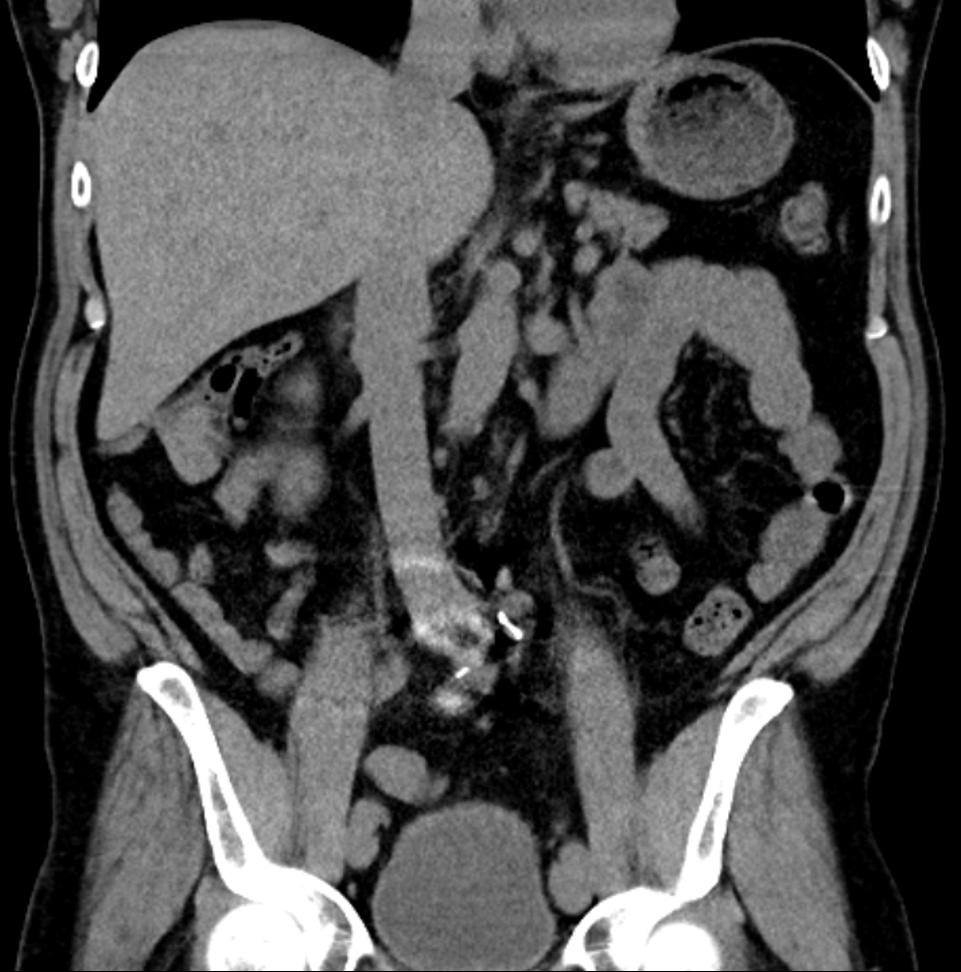

• Inyectando la fuente: Un caso de dolor abdominal resuelto mediante inyección de esteroides en el nervio cutáneo anterior